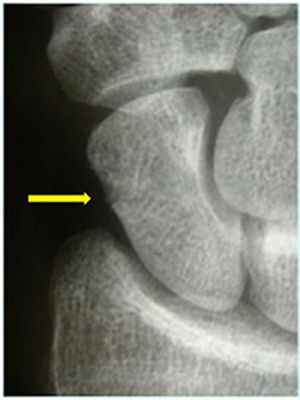

Рис. 1

Из-за своей формы и расположения это одна из наиболее часто ломающихся запястных костей. Перелом ладьевидной кости обычно происходит в результате падения на вытянутую руку, т.е когда ладонь распрямлена, а запястье выгнуто назад при падении на землю. Иногда перелом ладьевидной кости вызван ударом по кисти. В некоторых случаях многократная нагрузка на ладьевидную кость может привести к её перелому. Это происходит, к примеру, у гимнастов или толкателей ядра.

Диагностика: Иногда довольно сложно определить перелом ладьевидной кости. Обычный рентгеновский снимок может не показать перелом ладьевидной кости (рис. 2). При наличии симптомов и отрицательном результате рентгенографии применяются специальные виды исследований при локтевом отведении кисти. Если симптомы указывают на перелом ладьевидной кости, но он не подтверждается рентгеновскими снимками, то рекомендуется иммобилизация и повторный рентген спустя 10-14 дней. Если инструментальная диагностика не дала чёткого ответа проводится компьютерная томография или МРТ.